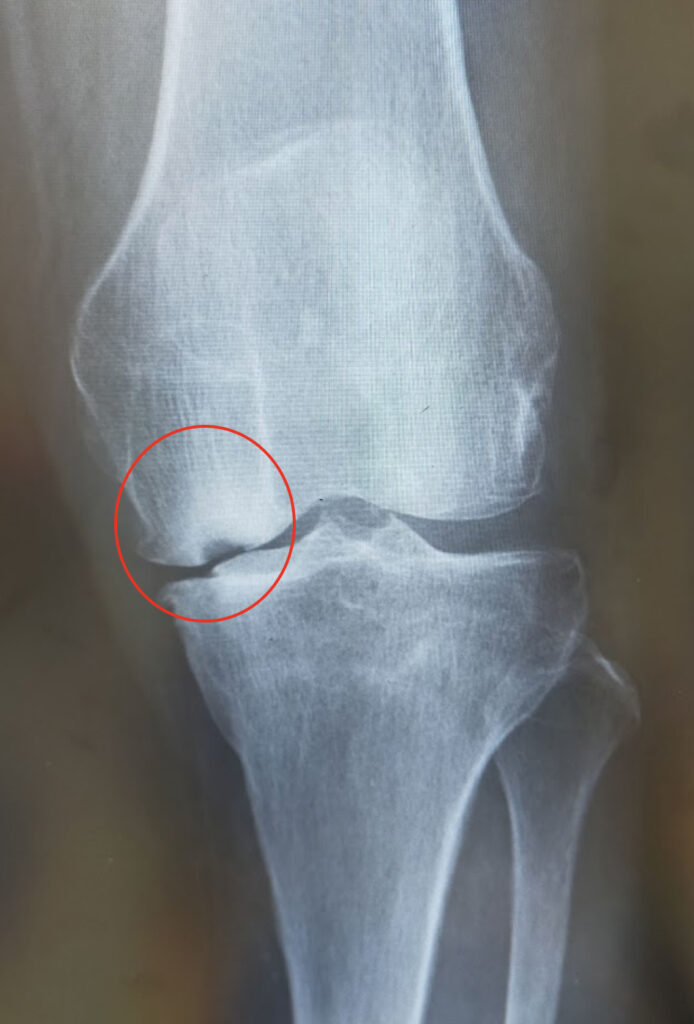

大腿骨顆部は体重を支えるのに重要で、過度なストレスが加わり壊死に陥ることがあります。

原因としてステロイド投与や半月板損傷後などに脆弱性骨折(軽微な外傷により軟骨下骨に微小骨折を生じる)が起こり壊死に至るとされています。安静にしていても痛みが出たり、夜間寝ている間に痛みが出ることもあります。

大腿骨顆部骨壊死のレントゲン